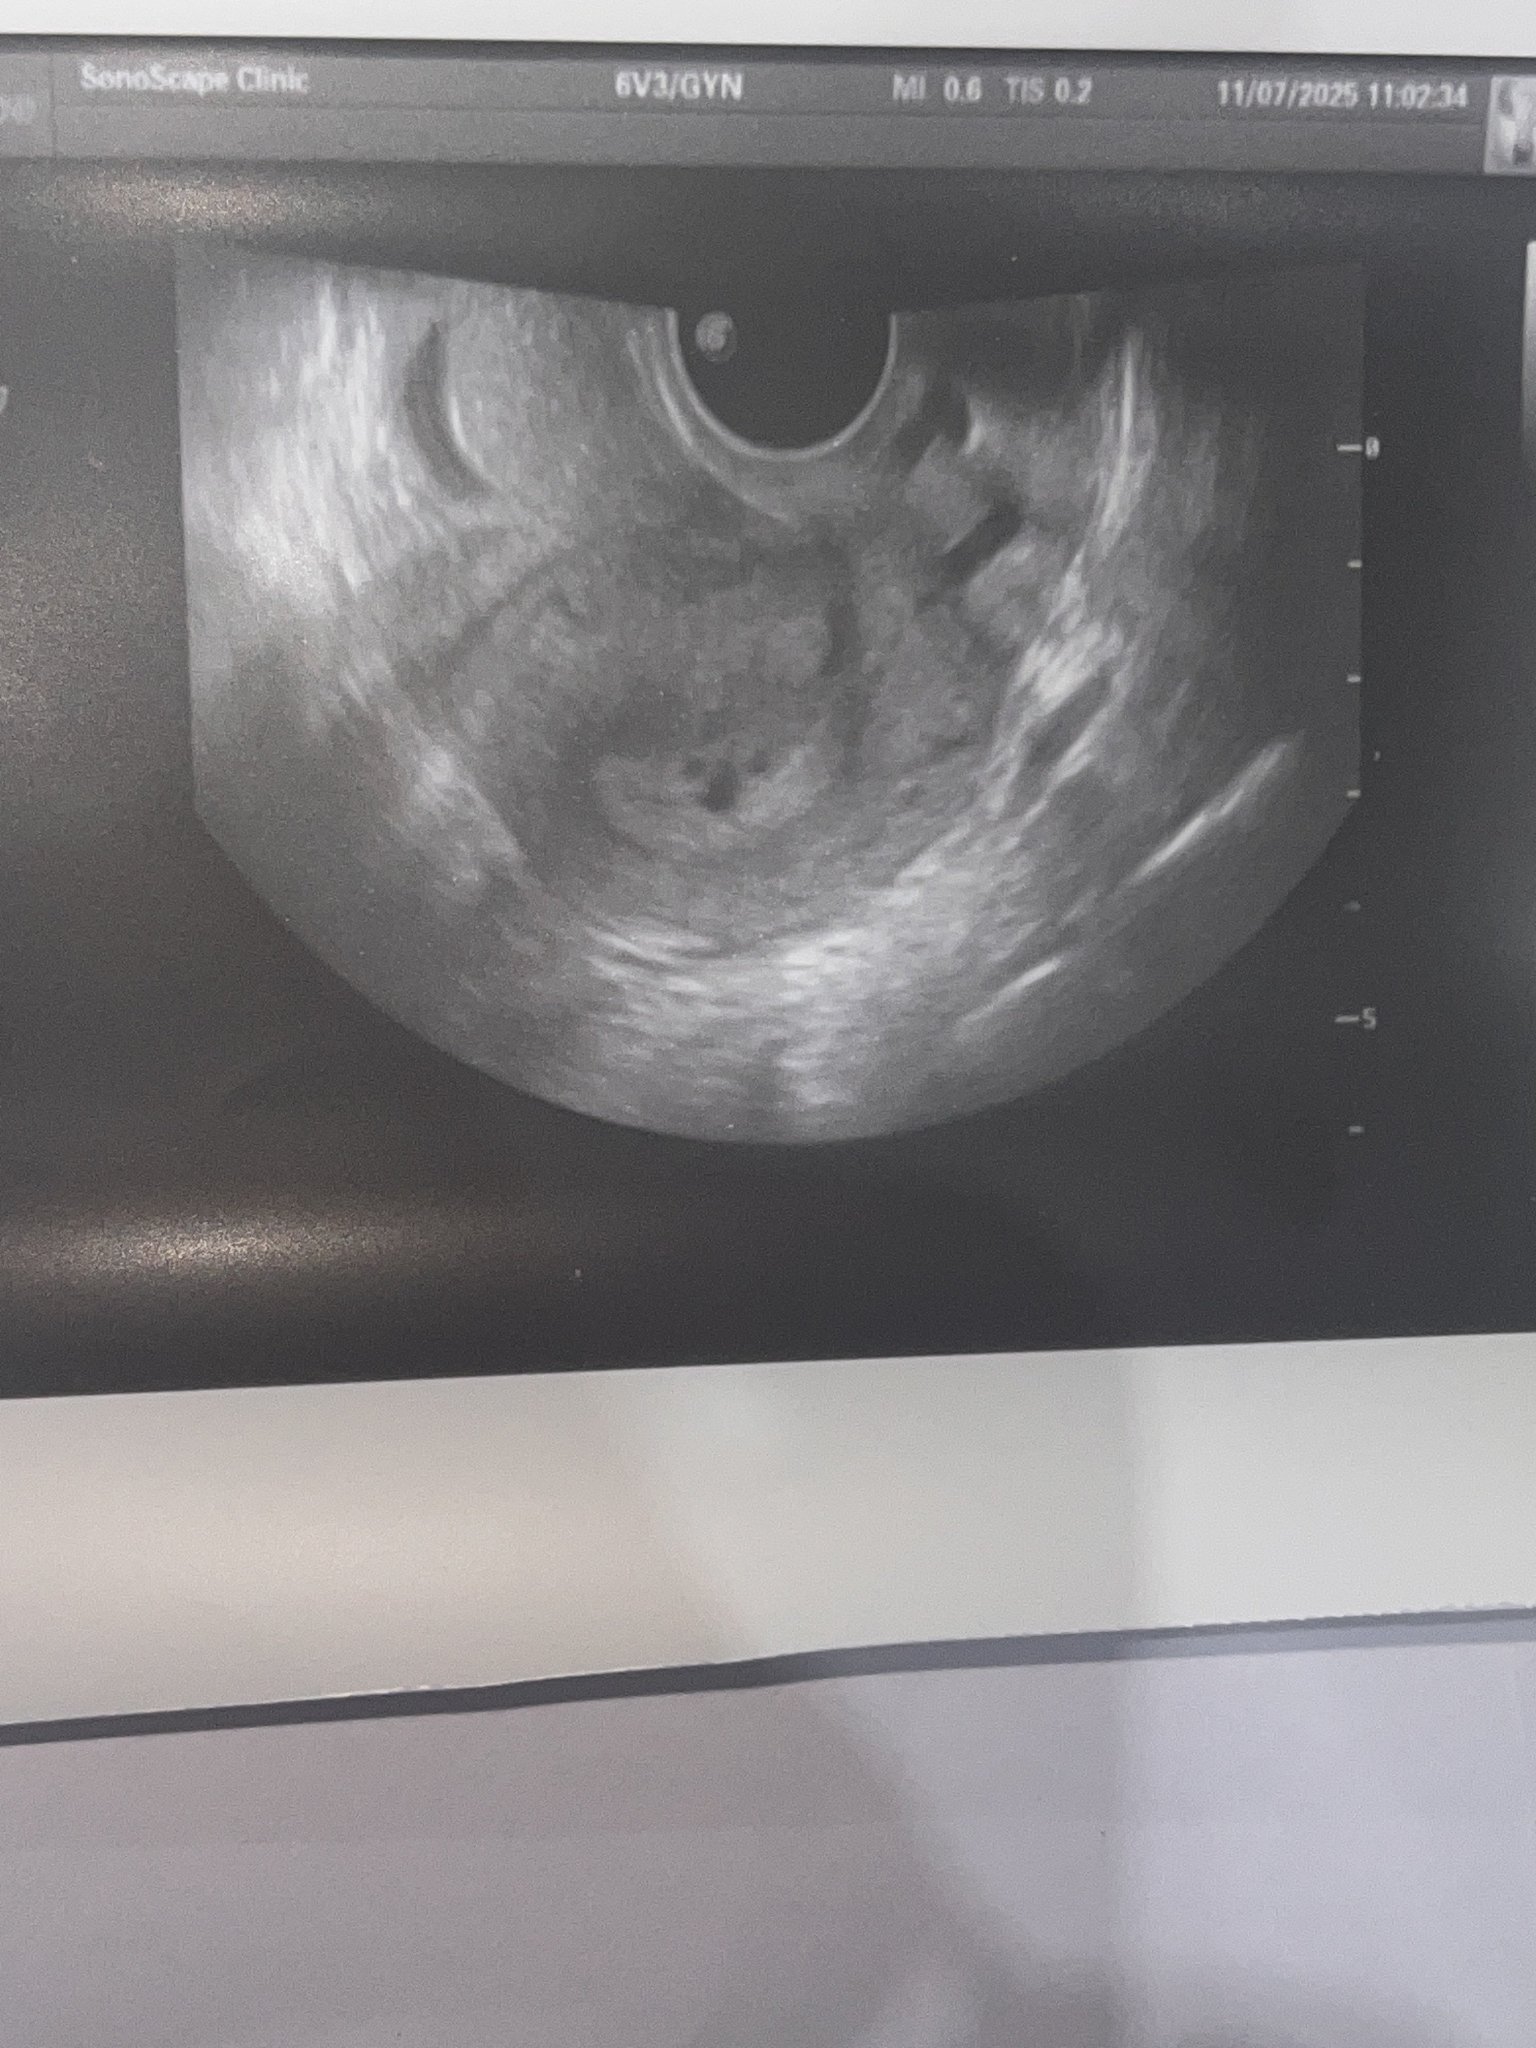

Кога обикновено може да се види ембрионът на ултразвукова снимка?